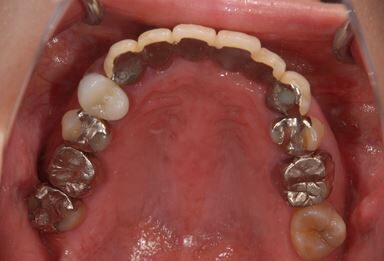

インプラントの症例写真 IMPLANT

骨再生インプラント治療

| カテゴリー | 【インプラント治療】【セラミック治療】 | ||||||||||||||||||||||||||||||||

| 性別/年齢 | 女性 / 40歳 | ||||||||||||||||||||||||||||||||

| 主訴 | 右下のブリッジが外れているかもしれないという診断を受けましたが、開けてみないとわからない、場合によっては部分入れ歯と言われ、セカンドオピニオンを希望。腫れがあるのも気になります。 | ||||||||||||||||||||||||||||||||

| 治療方針 | 右下奥、骨再生法によりインプラント治療を可能にする。 | ||||||||||||||||||||||||||||||||

| 治療内容 | インプラント3本(GBR、テンポラリーインプラント+仮歯)、ハイブリッドセラミックブリッジ3本、ハイブリッドセラミッククラウン2本 | ||||||||||||||||||||||||||||||||

| 総治療費 | 1,524,338円 | ||||||||||||||||||||||||||||||||

| 治療期間 | 1年0ヶ月 |